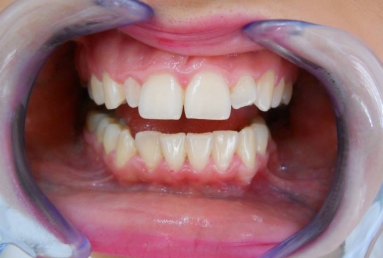

Very small lateral incisors covered with full ceramic crowns and ceramic veneers on central incisors. The prosthetic space was correctly split between the four incisors, in order to reduce the disproportion between the large centrals and the very small laterals. The preparation of the teeth was minimally invasive, all four incisors remained vital.